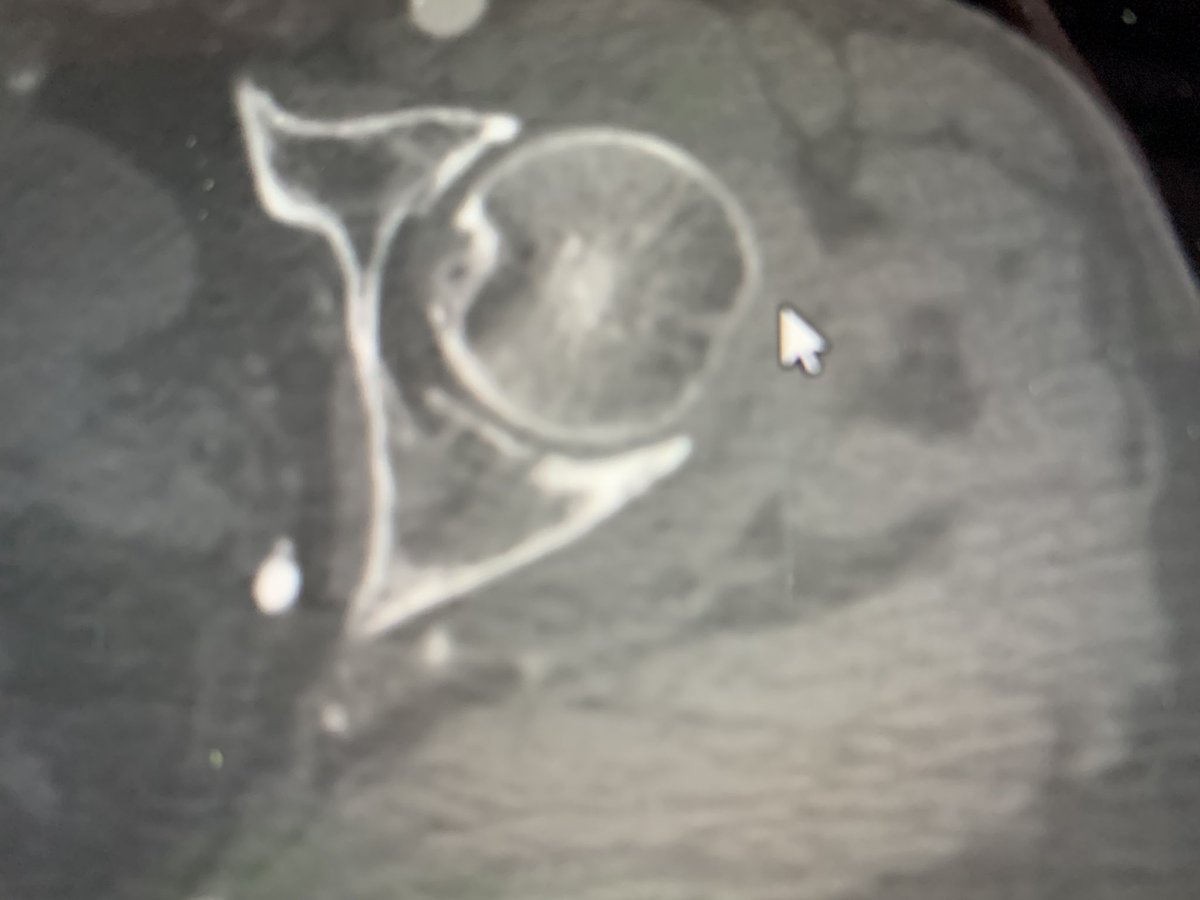

Segmental open femur fracture with ipsilateral non-displaced transverse acetabular fracture

CT negative / intra-op fluoro negative for fracture of the femoral neck

Patient returns to surg 4 weeks with femoral neck fracture